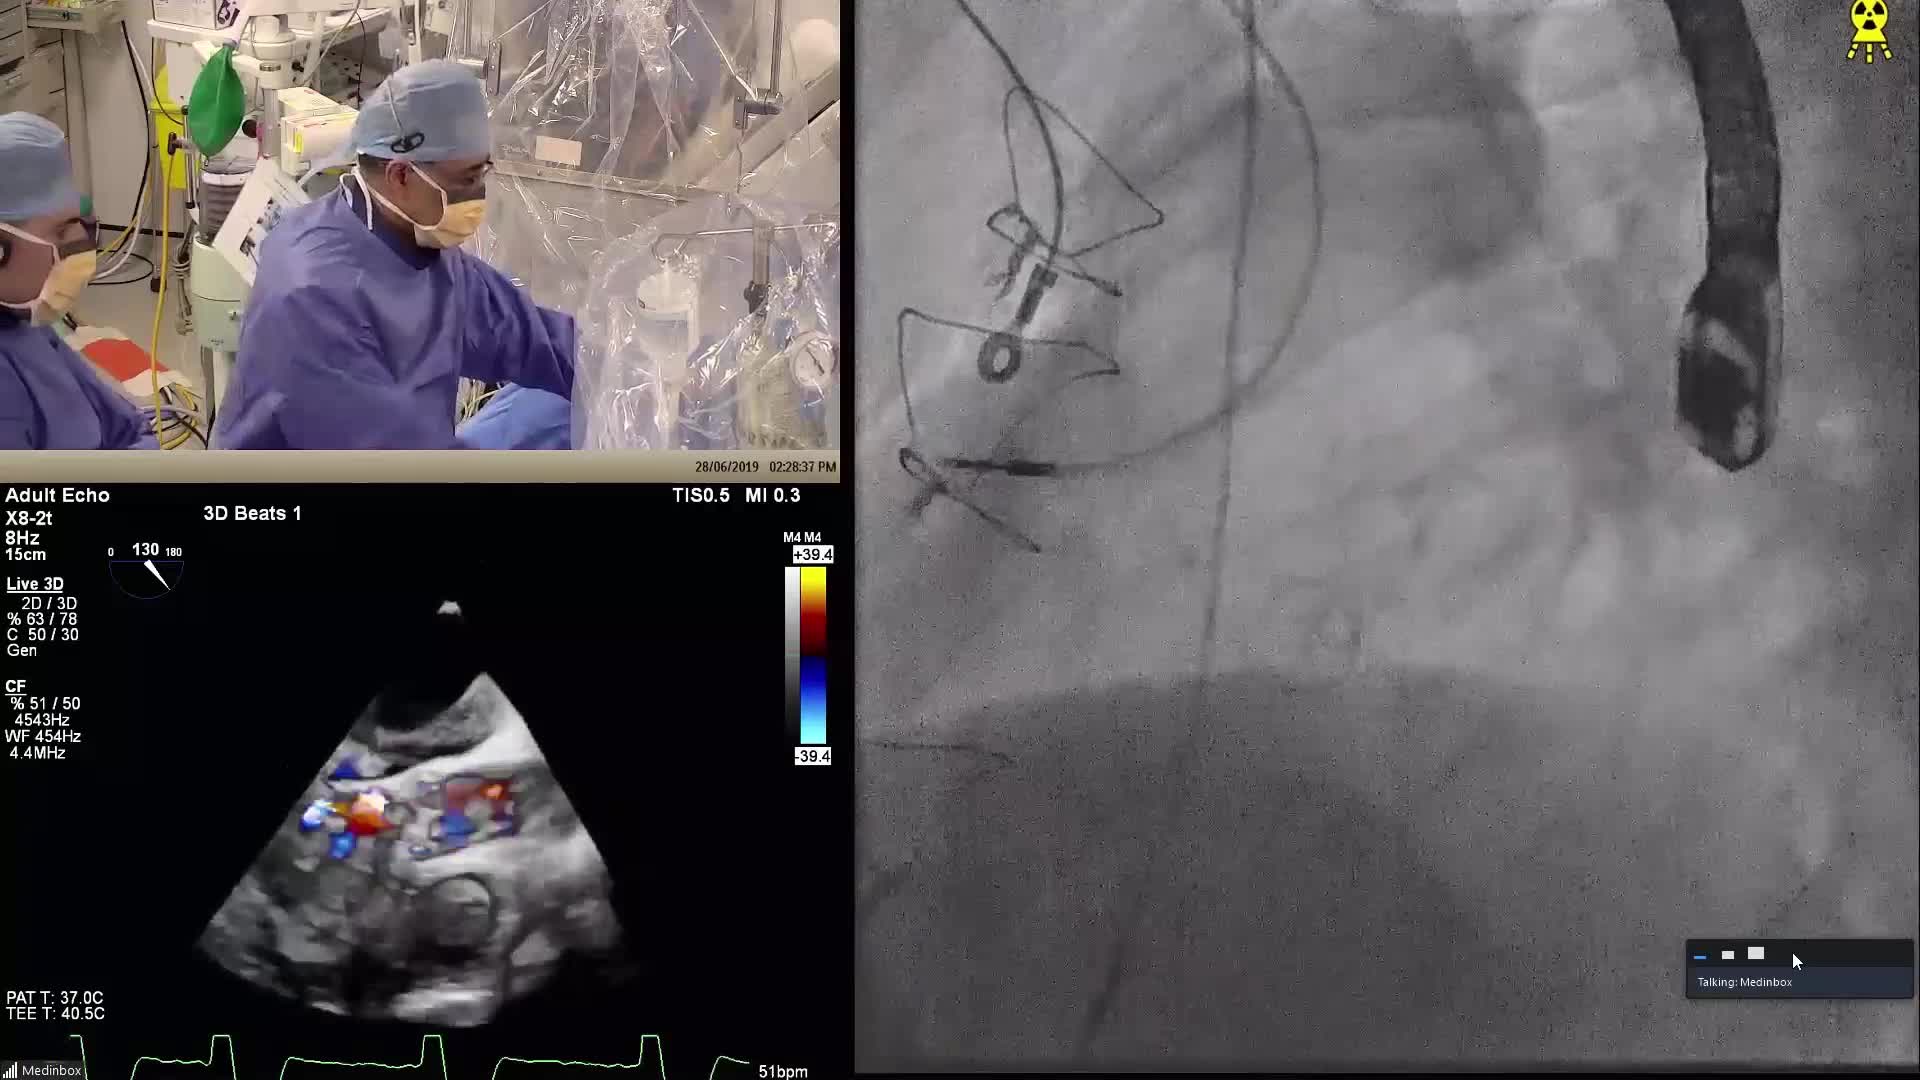

CSI CATHLAB LIVE - VSD CLOSURE WITH THE NEW OCCLUTECH PMVSD OCCLUDER (ANTEGRADE APPROACH)